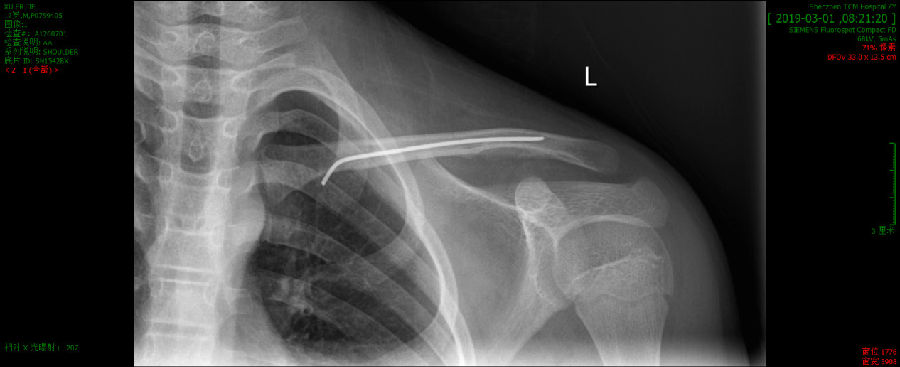

2月28日顺利实施手术,随后经过深圳市中医院各项中医特色理疗,术后第2日,患者就恢复了生活自理。

术后X线复查,骨折解剖复位